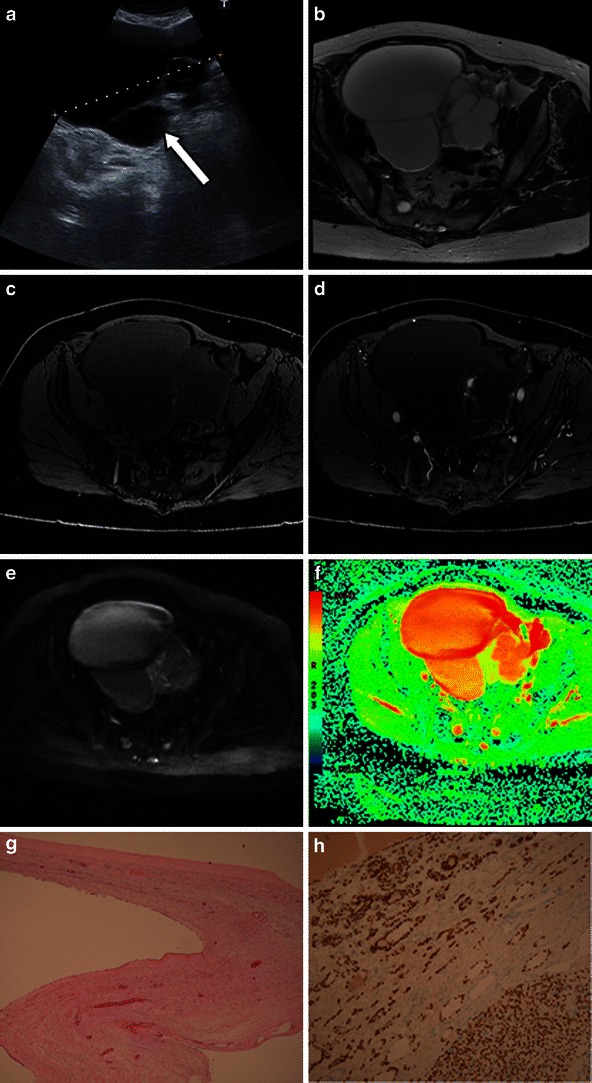

A non-cystic struma usually appears as a soft tissue mass, either as a solitary finding or more commonly against a background of a dermoid cyst. Very rarely struma ovarii falls into the category of cystic struma based on its macroscopic appearance. Yen et al. [29] reported one case of a struma ovarii with features on MR imaging that were indistinguishable from a benign multi-cystic ovarian tumour. Only a few cases of cystic struma ovarii have been reported in the literature [29–32]. On MRI, a cystic struma ovarii resembles a cystic epithelial ovarian lesion (Fig. 7). The diagnosis of a cystic struma ovarii is usually made on histopathology. It is recommended that cystic struma ovarii should be considered when evaluating cystic ovarian tumours whose features are not obviously those of another tumour type. If this is the case, a careful search for thyroid follicles should be undertaken. Immunohistochemical staining for thyroglobulin in difficult cases is recommended [32].

Fig. 7.

Benign cystic struma ovarii in an 81-year-old woman, presenting with abdominal swelling and discomfort and normal CA125. a Ultrasound shows thick septations (arrow) within a cystic lesion. Three-tesla T2-weighted high-resolution images (b), unenhanced (c) and enhanced (d) T1 fat-saturated LAVA, diffusion-weighted images b = 1,200 mm/s2 (e) and corresponding ADC map (high ADC values shown in red) (f) through the same slice are shown. The case macroscopically mimicked a cystadenoma. g On histological examination, however, although the cyst loculi were lined by flattened low columnar indifferent epithelium, there were several small areas where micro- and macro-follicles of thyroid tissue were evident. The diagnosis was confirmed with the aid of positive immunostaining for both thyroglobulin (h) and TTF1 antibodies. No other teratomatous component was identified despite review of the tissue blocks